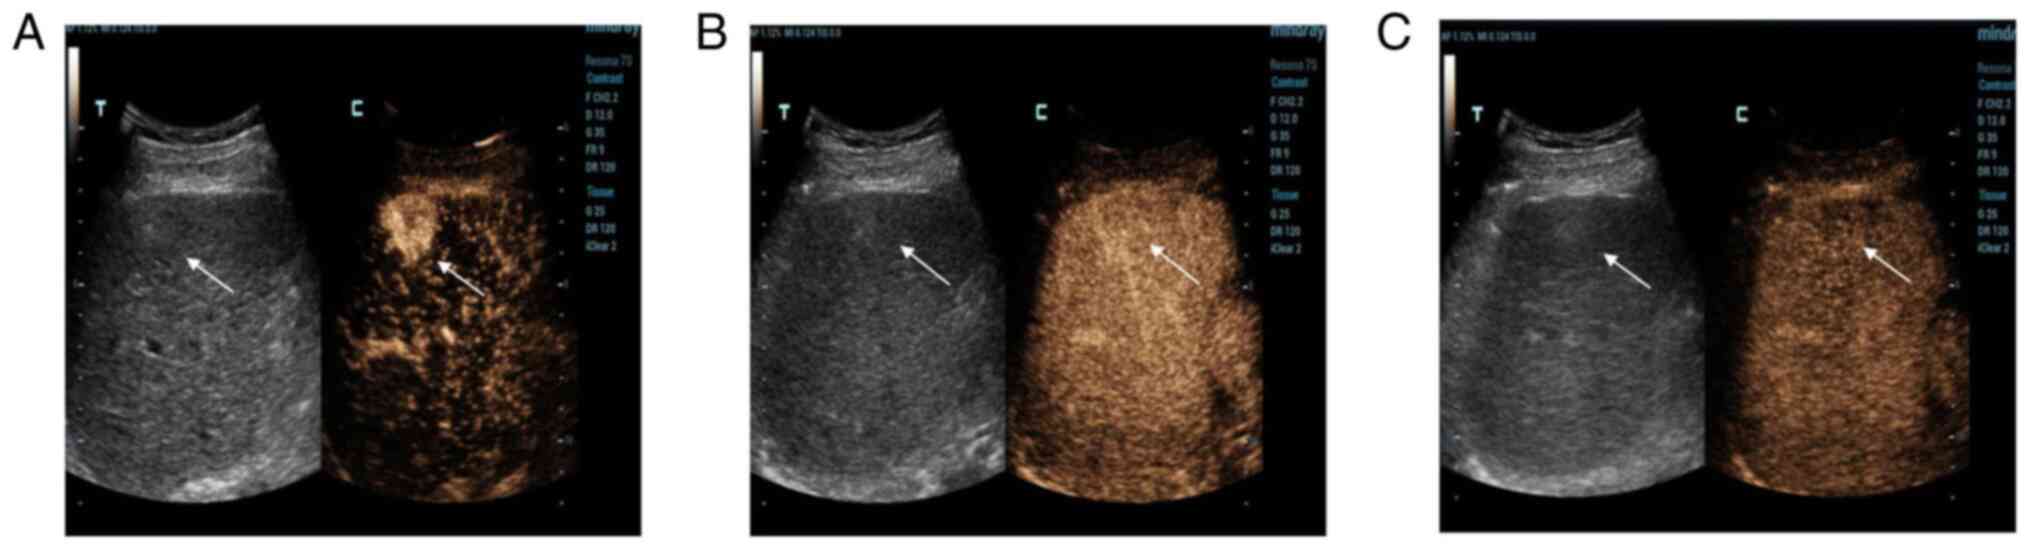

Imaging analysis of the malignant transformation of bile duct hamartomas in the liver: A case report and literature review

Bile duct hamartoma in the liver (LBDH) is relatively rare among the hepatic space‑occupying lesions that occur in adults, and the malignant transformation of LBDH is even rarer. In the present case report, a 63‑year‑old male was found to have two space‑occupying lesions in the right lobe of the liver upon ultrasound examination. Enhanced computed tomography (CT) suggested benign hepatic haemangioma, and contrast‑enhanced ultrasonography (CEUS) suggested well‑differentiated hepatocellular carcinoma. The final pathology results revealed the malignant transformation of LBDH into well‑differentiated intrahepatic cholangiocarcinoma. Improved recognition of this type of rare disease can be obtained by radiographic analysis of this case. These findings contribute to a better understanding of the enhanced development pattern of this disease on contrast‑enhanced CT, as well as on CEUS.